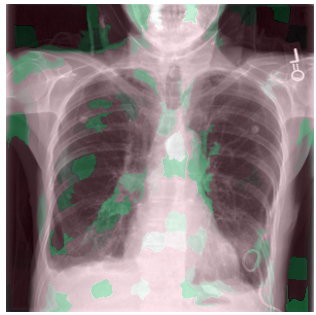

3.3 Interpretability

Post-Hoc Comparisons. We compare our concept-based explanations to post-hoc XAI techniques LIME and SHAP, applied to the baseline InceptionV3 model. The image explanations generated by these techniques disagree with each other and the medical ground truth. We show an example of this observation in Figure 7, where both techniques fail to capture the large mass in the X-ray, and highlight irrelevant regions such as areas outside of the lung as incorrectly important to the classification decision. In contrast, our approach correctly identifies the presence of a mass. More examples are shown in Figure 10.

Refer to caption

(a) Ground Truth

(b) LIME

(c) SHAP

(d) CXR-LLaVA Generated Report

(e) Our Approach

Figure 7: Example of our explanation approach outperforming LIME, SHAP and CXR-LLaVA. Ground truth (a) is a “Large right upper zone mass". LIME (b) and SHAP (c) fail to capture the mass in the X-ray. Most important image regions are bounded by yellow for LIME, and shown in more vibrant green for SHAP. CXR-LLaVA (d) generates a report which wrongly describes the image as non-cancerous. Our approach (e) correctly identifies the presence of a mass.

(a) Ground Truth 1

(b) Ground Truth 2

(c) Ground Truth 3

(d) Ground Truth 4

(e) LIME 1

(f) LIME 2

(g) LIME 3

(h) LIME 4

(i) SHAP 1

(j) SHAP 2

(k) SHAP 3

(l) SHAP 4

Figure 10: Examples of LIME and SHAP explanations failing to capture the medical ground truth of a cancerous chest X-ray, while also generating conflicting explanations. Ground truth (a,b,c,d) is shown as red squares. Most important regions are bounded by yellow for LIME (e,f,g,h) and shown as more vibrant green for SHAP (i,j,k,l).